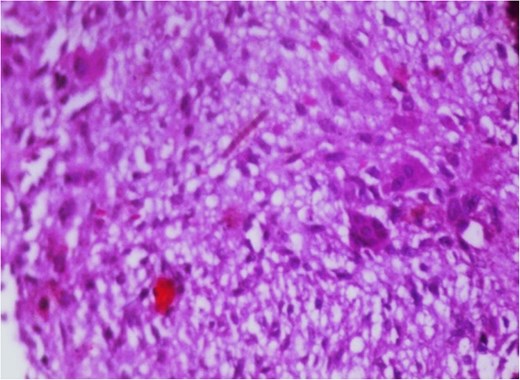

Additionally, magnetic resonance venography (MRV) confirmed a patent superior sagittal sinus with no encroachment of the lesion (Fig. 4). Differential diagnoses included dermoid cyst, eosinophilic granuloma, or benign fibro-osseous lesion. Surgical intervention involved en bloc excision under general anesthesia. A curvilinear incision was made over the mass, followed by subperiosteal dissection, which confirmed the lesion’s confinement to the diploë. Intraoperative frozen section analysis was not performed due to the lesion’s benign radiological features. Histopathological examination confirmed NOF, demonstrating ectodermal inclusion, cellular stroma of spindle-shaped fibroblasts arranged in a prominent storiform pattern, and scattered osteoclast-like giant cells. Notably, no evidence of mitotic figures, nuclear atypia, or necrosis was observed (Figs 5–7). The margins were free of lesional tissue. Postoperatively, the child resumed oral intake within 4 hours and was discharged on postoperative day 2 with analgesics. At the 6-month follow-up, the wound had healed without complications, with no recurrent lesion.

Photomicrograph in a case of NOF showing interlacing bundles of spindle-shaped fibroblasts in a storiform manner, H&E × 400.